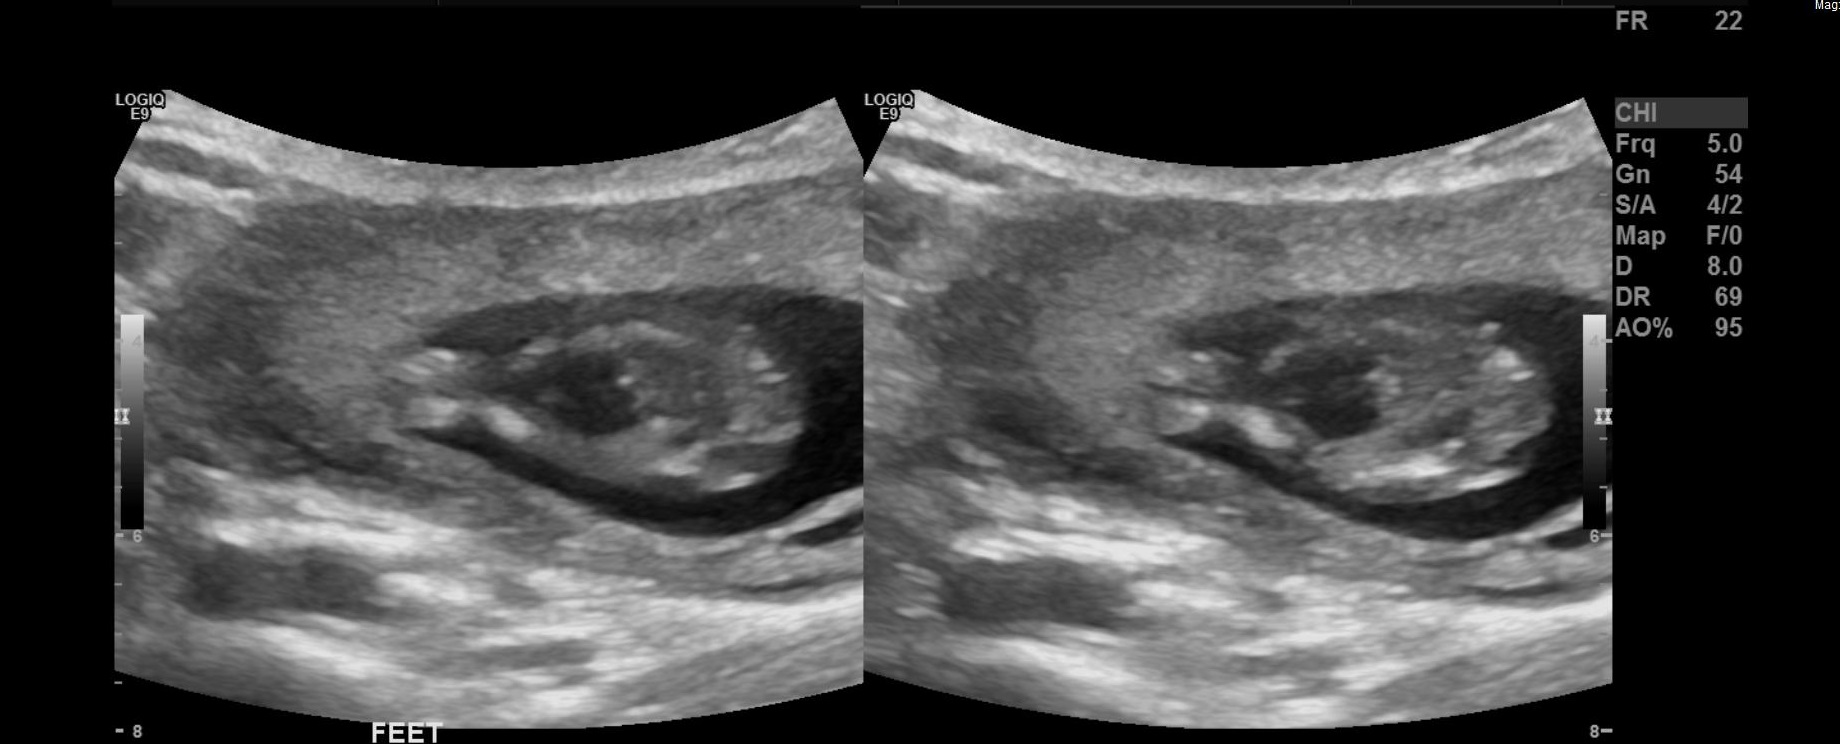

14 week potty shot, Confused with both pictures

Hi all, 14 weeks and I have a potty shot of my baby .

I'm confused with the pictures , same shots but both pictures look completely different.

Most are saying girl and the tech referenced it as "she"

But after looking at the left picture that looks like a boy??

Any insight until i get another scan , I'm obsessing over this lol

Any guesses are welcome and appreciated, Skull theory seems to point boy and The little one wouldn't stay still for a nub shot , ive only got an upside down shot and i think that voids the nub theory !